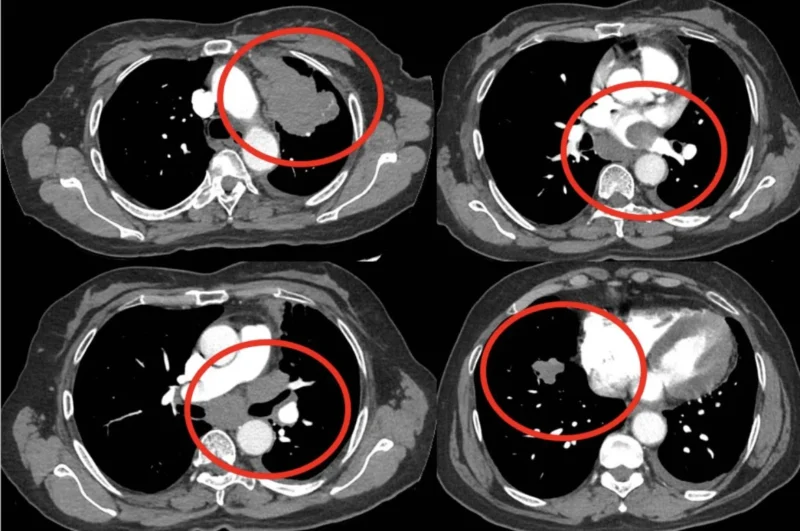

Evaluation with CTA showed no PE but demonstrated a very large LUL mass with direct extension into mediastinum and L atrium and additional R sided lung lesions c/w st4 disease.

Cardiac MR and ECHO confirm a mobile mass in L atrium contiguous w LUL mass. Path shows lung adenoca, PD-L1 TPS score >90%, ctDNA+ for K-Ras G12C.